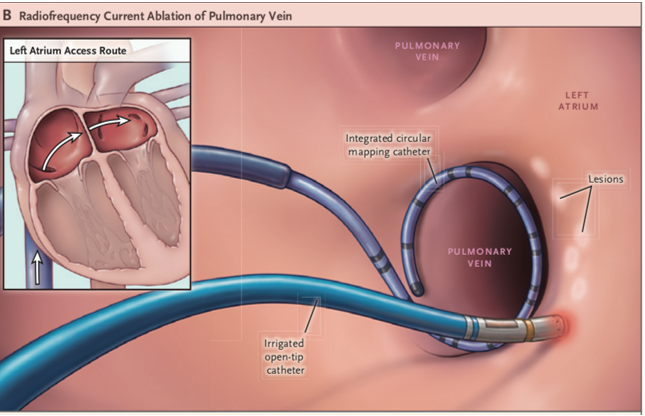

高周波アブレーションという高周波電流を通電して焼灼する方法以外に、心房細動の初回症例や発作性上室頻拍の一部(房室結節リエントリー性頻拍)に対する治療として、冷凍アブレーション(クライオアブレーション)を積極的に取り入れ、より安全な治療を心がけています。

さらに、昨年9月より保険適応となり使用可能になったパルスフィールドアブレーションは従来の熱アブレーション(高周波アブレーション:高周波電流で組織に熱を発生させ焼灼する、クライオアブレーション:冷却されたバルーンを組織に押し当て冷凍凝固を行う)とは異なるエネルギー(パルス電圧)にて心房細動の原因となる心房筋を選択的に焼灼する新しい治療法です。パルスフィールドアブレーションは心筋細胞特異的に焼灼を行うことが可能であるため肺静脈、食道や横隔神経などの周辺組織に関する合併症の発生リスクを低減することが期待されています。パルスフィールドアブレーションは当院でも本年2月より使用可能となりました。今後はそれぞれの患者さんの病態に応じた治療の選択肢が増え、より患者さんに適した治療を選択できるようになりました。

Cryoballoon or Radiofrequency Ablation for Paroxysmal Atrial Fibrillation.

N Engl J Med. 2016;374(23):2235-45. より引用